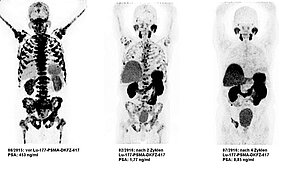

Das Bild zeigt die Wirkung einer Lutetium-177-PSMA Therapie innerhalb von vier Zyklen. Schwarz sind die Krebszellen markiert.

Im Dezember 2022 hat die Europäische Arzneimittelkommission das Radiopharmakon Lutetium-177-PSMA zur Behandlung von Patienten mit fortgeschrittenen Prostata-Krebs zugelassen. Danach ging es schnell. Expertinnen und Experten der Bayreuther Nuklearmedizin setzen das Präparat, das den Patienten über die Armvene in mehreren Zyklen, jeweils im Abstand von mehreren Wochen, verabreicht wird, bereits seit einigen Monaten erfolgreich ein. Und die Ergebnisse sind vielversprechend. Gerade weil zielgerichtete Diagnostik und Therapie dabei kombiniert- und die Patienten, die von dieser Therapie am besten profitieren bereits in der vorgeschalteten PSMA-PET/CT-Ganzkörperdiagnostik vor Einleitung der Therapie identifiziert werden können. Damit wird eine neue Qualitätsstufe erreicht.

„Das Prinzip entspricht dem von passenden Schlüssel und Schloss“, sagt Prof. Dr. Förster. Das diagnostisch einsetzbare Gallium-68- oder Fluor-18-PSMA dockt gezielt an prostataspezifische Membranantigene (PSMA) an. An der Oberfläche von Prostatakrebszellen sind diese PSMA-Eiweiße überdurchschnittlich stark vorhanden. Größere oder kleinere Areale, dunklere oder hellere Anreicherungen - Nuklearmediziner sehen anhand der Schnittbilder aus hochmodernen PET/CT-Bildgebungsmaschinen, wie ausgedehnt und wie aggressiv der Krebs ist. Und: Weil das Gallium-68- oder Fluor-18-PSMA über das Gefäßsystem im gesamten Körper verteilt wird, dockt es nicht nur am Primärtumor sondern auch an den entfernt gelegensten Metastasen an. Damit lässt sich innerhalb einer einzigen Untersuchung u.a. auch die bange Frage beantworten: Hat der Krebs gestreut?

Auch hier gilt das Prinzip von passenden Schlüssel und Schloss und die Verteilung über das Gefäßsystem in den gesamten Körper ist für das therapeutische Radiopharmakon identisch wie bei der Diagnostik. Beim Andocken an die Krebszelle belässt es das therapeutisch wirksame Lutetium-177-PSMA jedoch nicht. Vielmehr dringt es durch die Zellmembran ein, Mediziner sprechen von einer Internalisierung. Der Betastrahler Lutetium-177 mit seiner hochenergetischen Strahlung in kurzer, nur Millimeter betragender Reichweite schädigt die DNA der Krebszelle. Und diese stirbt dabei ab. „Der Vorteil ist offensichtlich“, sagt Prof. Dr. Förster. Die Strahlen wirken direkt in der Krebszelle, die Dosis kann damit höher gewählt werden und die Behandlung ist trotzdem schonender als dies beispielsweise eine konventionelle Bestrahlung von außen sein kann. Denn bei einer konventionellen Bestrahlung von außen gilt es, auf gesundes Gewebe maximale Rücksicht zu nehmen um dieses nicht zu schädigen.